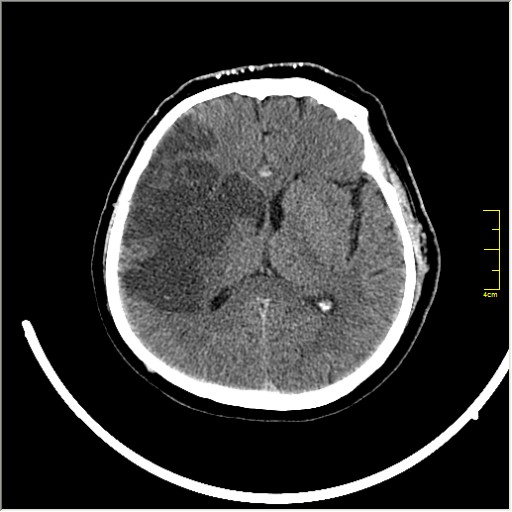

Этот признак называется [Dense MCA sign]; за счёт наличия тромбоза в её просвете. Этот признак является одним из ранних указующих КТ признаков при ишемическом инфаркте головного мозга. Более подробно об этом вы можете прочитать здесь: http://www.radiologyassistant.nl/en/483910a4b6f14.

Ну и для полноты картины, привожу контрольные КТ сканы выполненные через 24 часа: